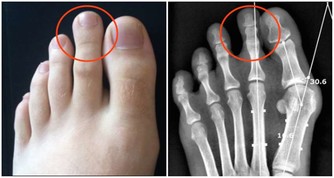

如果身體某一部位突然疼痛,持續一個多星期,應盡快查明原因。例如,長期腹痛是大腸癌的症狀;胸痛可能是肺癌引起的;骨痛可能是癌症轉移的症狀。這時,我們應該去醫院找醫生檢查一下。